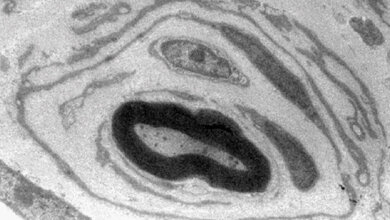

Die häufigste Form der Charcot-Marie-Tooth-Krankheit (CMT) ist CMT1A. Hierbei liegt ein Gendefekt vor, bei dem das periphere Myelin-Protein (PMP) 22 doppelt vorliegt. Patientinnen und Patienten entwickeln dadurch langsam fortschreitende Nervenschädigungen, die bereits im Kindheitsalter beginnen und mit einer Muskelschwäche und dem Muskelabbau einhergehen. Infolge dessen leiden die Betroffenen an Gehschwierigkeiten oder Fußdeformitäten, später an Sensibilitätsstörungen wie Taubheit, Kribbeln und Schmerzen. In manchen Fällen ist ein Rollstuhl notwendig und trotz Fortschritten in der Diagnostik, gibt es keine Therapie für CMT.

Für die Studie werden Blutproben von Patientinnen und Patienten mit CMT1A sowie Haut- und Nervengewebeproben eines CMT1A-Tiermodells mittels MRT und Mutli-Omics-Analysen untersucht. Stimmen die Studienteilnehmerinnen und -teilnehmer zu, werden bei ihnen mittels Stanzprobe ebenfalls Hautproben entnommen. Mithilfe der Multi-Omics-Analyse werden Datensätze von Biomolekülen von RNA-Sequenzen, Proteinen und Fetten untersucht sowie biologische Zusammenhänge ermittelt. Anschließend sollen diese Daten mit MRT-Aufnahmen kombiniert werden.